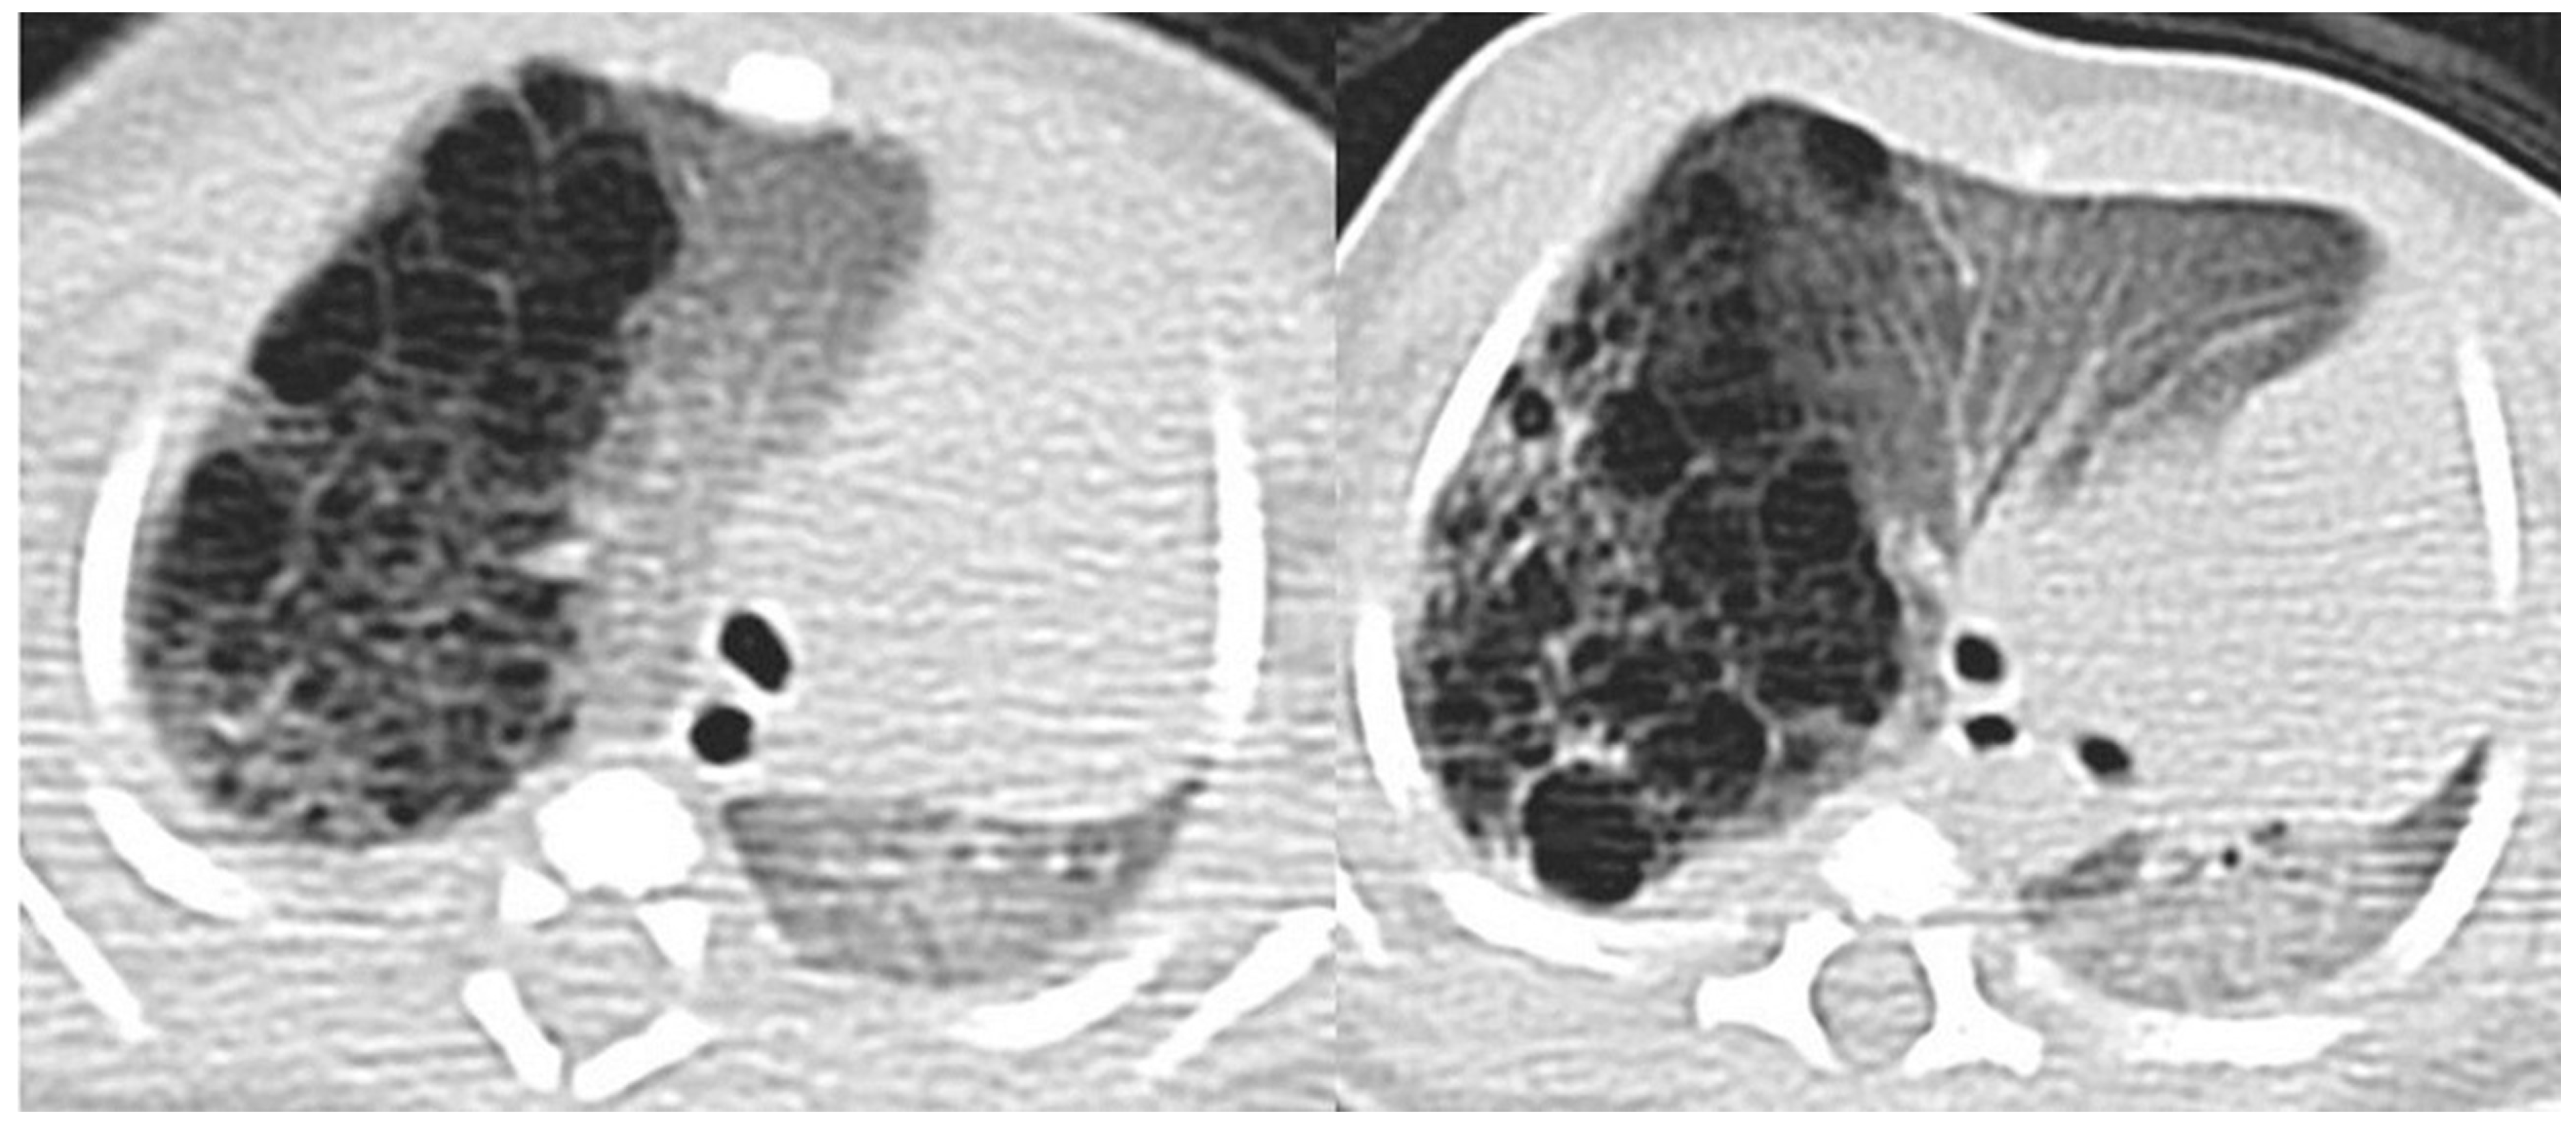

Axial CT scan performed on a 4 month old female patient, depicting a type 1 CPAM. In image (a), it is possible to appreciate a large (>2 cm) air-filled cyst, surrounded by other multiple smaller cysts. Additionally, in image (b), a coronal CT MinIP reconstruction of the same patient is shown, which excludes communication with the tracheo-bronchial tree.

Figure 7.

A CT scan later performed in the same patient as in Figure 4, showing multiple small air-filled cysts in the right upper lobe and in the right lower lobe, with a maximum diameter of 20 mm, confirming the diagnostic hypothesis of type 2 CPAM.